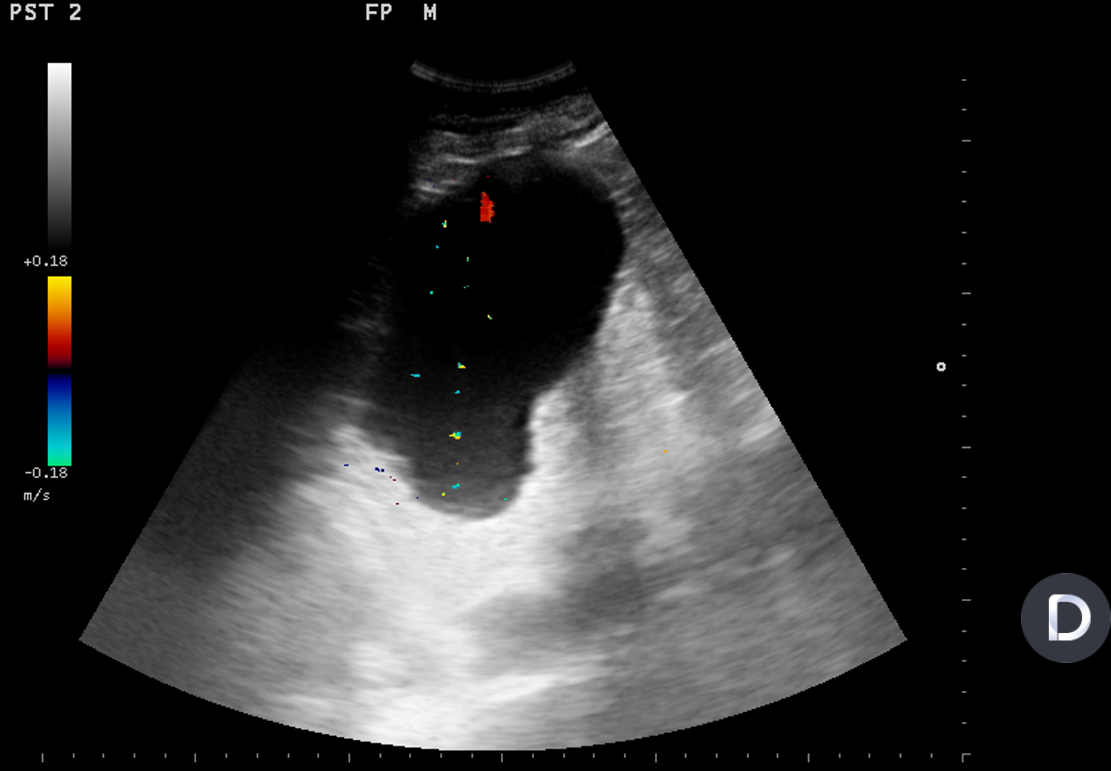

Se realiza ecografía renal a primaria que objectiva una imagen anecoica a nivel de polo superior de riñón izquierdo de 13 x 9 cm que no capta Doppler compatible com un quiste simple renal (Bosniak I).